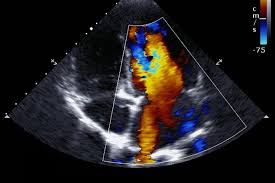

심장 초음파는 인체에 무해한 초음파를 이용해 실시간으로 이러한 심장의 움직이는 모습을 관찰할 수 있고 심장의 움직임과 구조, 혈류의 흐름, 판막의 이상 유무 등을 비침습적으로 관찰할 수 있는 검사법이라고 한다. 대부분의 심장 질환에 필수적인 검사며, 많은 심장질환에서 높은 정확도를 가진다고 한다.

심장 초음파로는 혈액의 역류를 막아주는 4개의 판막이 잘 열리고 잘 닫히는지, 구멍 등 이상 소견은 없는지, 혈액의 역류는 없는지 등을 확인할 수 있다고 한다.